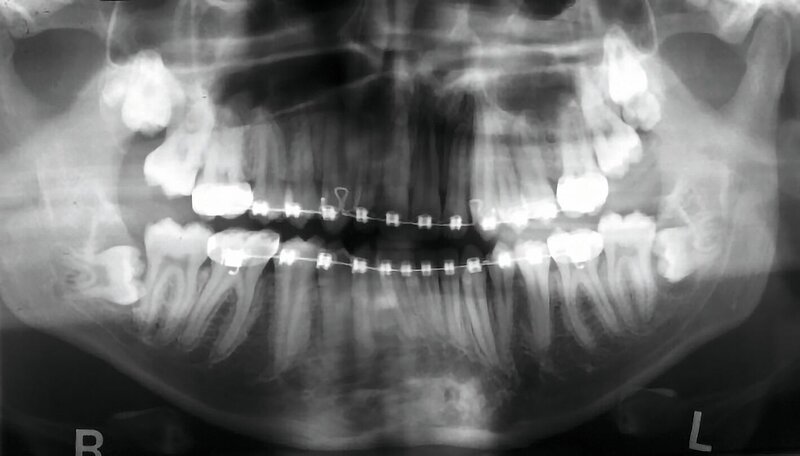

Neben der ausführlichen Anamnese und der klinischen Untersuchung ist eine röntgenologische Untersuchung wichtig. Zur Übersicht kann eine zweidimensionale Panoramaschichtaufnahme angefertigt werden, um die Lage und Angulation der Weisheitszähne sowie deren Beziehung zu ihren anatomischen Nachbarstrukturen beurteilen zu können [ARö/DGZMK, 2022; DGMKG, 2019].

Abbildung 1 zeigt ein Fallbeispiel einer Panoramaschichtaufnahme eines 18-jährigen Patienten mit den genannten röntgenologischen Anzeichen einer engen Lagebeziehung zum Nervkanal, zum einen in Regio 38, aber auch in Regio 48. Zudem befinden sich in Regio 18 und 28 unklare weitere zahnähnliche Strukturen.

Bei solch besonderen Risikosituationen kann gemäß den S2k-Leitlinien „Dentale digitale Volumentomographie“ und „Operative Entfernung von Weisheitszähnen“ eine dreidimensionale Bildgebung in Form einer digitalen Volumentomografie oder einer Computertomografie durchgeführt werden [ARö/DGZMK, 2022; DGMKG, 2019]. Mit der präziseren Visualisierung von Karies, Wurzelresorptionen, Wurzelpositionen und deren Morphologie sowie der Lagebeziehung zu den Nachbarstrukturen kann man die differenzialtherapeutische Entscheidungsfindung, die detaillierte Risikoaufklärung des Patienten und die Operationsplanung verbessern. Außerdem kann die Bildgebung vom Behandler intraoperativ genutzt werden, um sich zu orientieren.